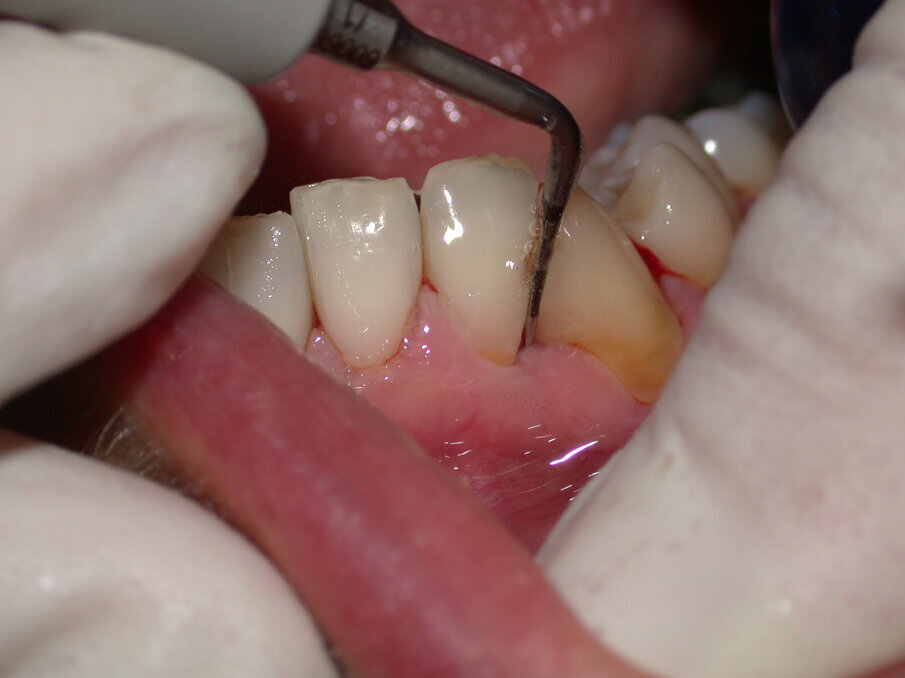

Fig. 2 - Debridement Parodontale con inserto specifico 10Z Acteon Satelec da utilizzare con basse e medie potenze.